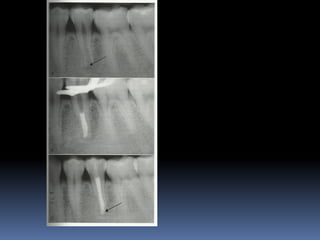

 This isthen covered with Glass ionomer and the tooth is restored with a restoration that seals completely  Follow up • No signs of irreversible pulpitis • No radiographic signs of o internal resorption o external resorption o calcification o periapical radioluscency

OPEN APEX  Anopen apex is the developing root of an immature tooth until apical closure occurs .  Apical closure occurs 2-3 yrs after tooth eruption  Any injury to the pulp at this stage will stop the closure of the apex  Such a tooth will have short , thin walls at the apical portion of the root

Diagnosis and assessment: History  Subjective symptoms  Diagnostic tests  Radio graphs A radiolucent area usually surrounds the apex of an immature root with a healthy pulp

The patient isthen put on a periodic recall for 1-2yrs at every 6 month interval. Commonly encountered • Calcific metamorphosis • Internal resorption In such cases NSRCT initiated.